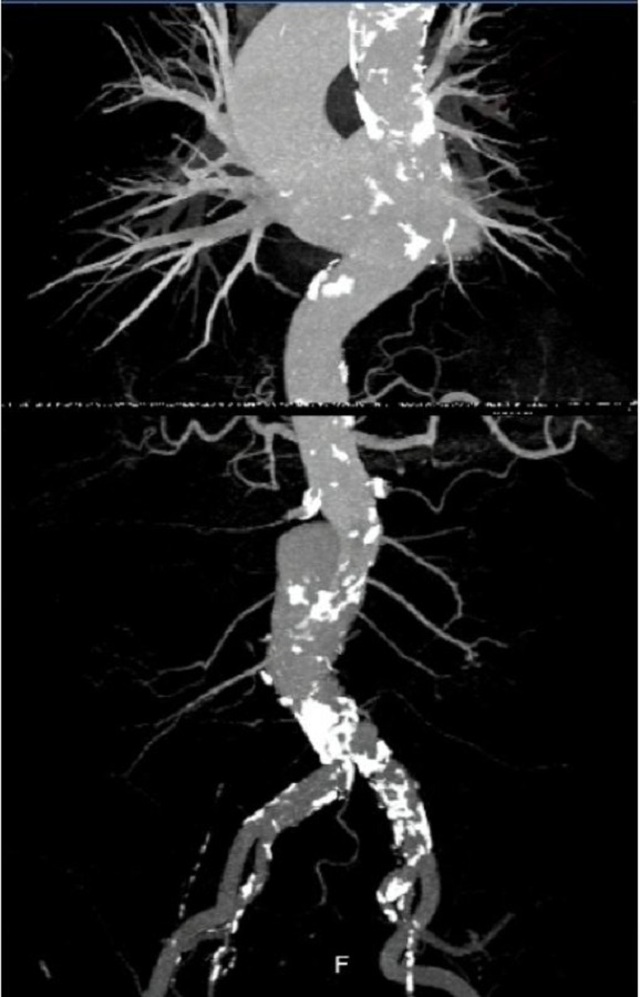

Hình ảnh động mạch chủ của người bệnh trên hệ thống chụp mạch máu xóa nền thời điểm trước can thiệp

Với sự hỗ trợ của hệ thống chụp mạch máu xóa nền, ê kíp bác sĩ đã đặt thành công stent vào vị trí túi phình động mạch chủ bụng cho người bệnh. Thiết bị là một khung giá đỡ bằng kim loại được phủ bởi màng sợi tổng hợp trong lòng của túi phình để tái tạo thành động mạch bị tổn thương, đồng thời điều chỉnh dòng chảy đúng sinh lý hơn, ngăn chặn nguy cơ vỡ túi phình. Sau can thiệp, sức khỏe bệnh nhân bình phục rất tốt.

Các bác sĩ đã đặt thành công stent ngăn chặn nguy cơ vỡ túi phình cho bệnh nhân